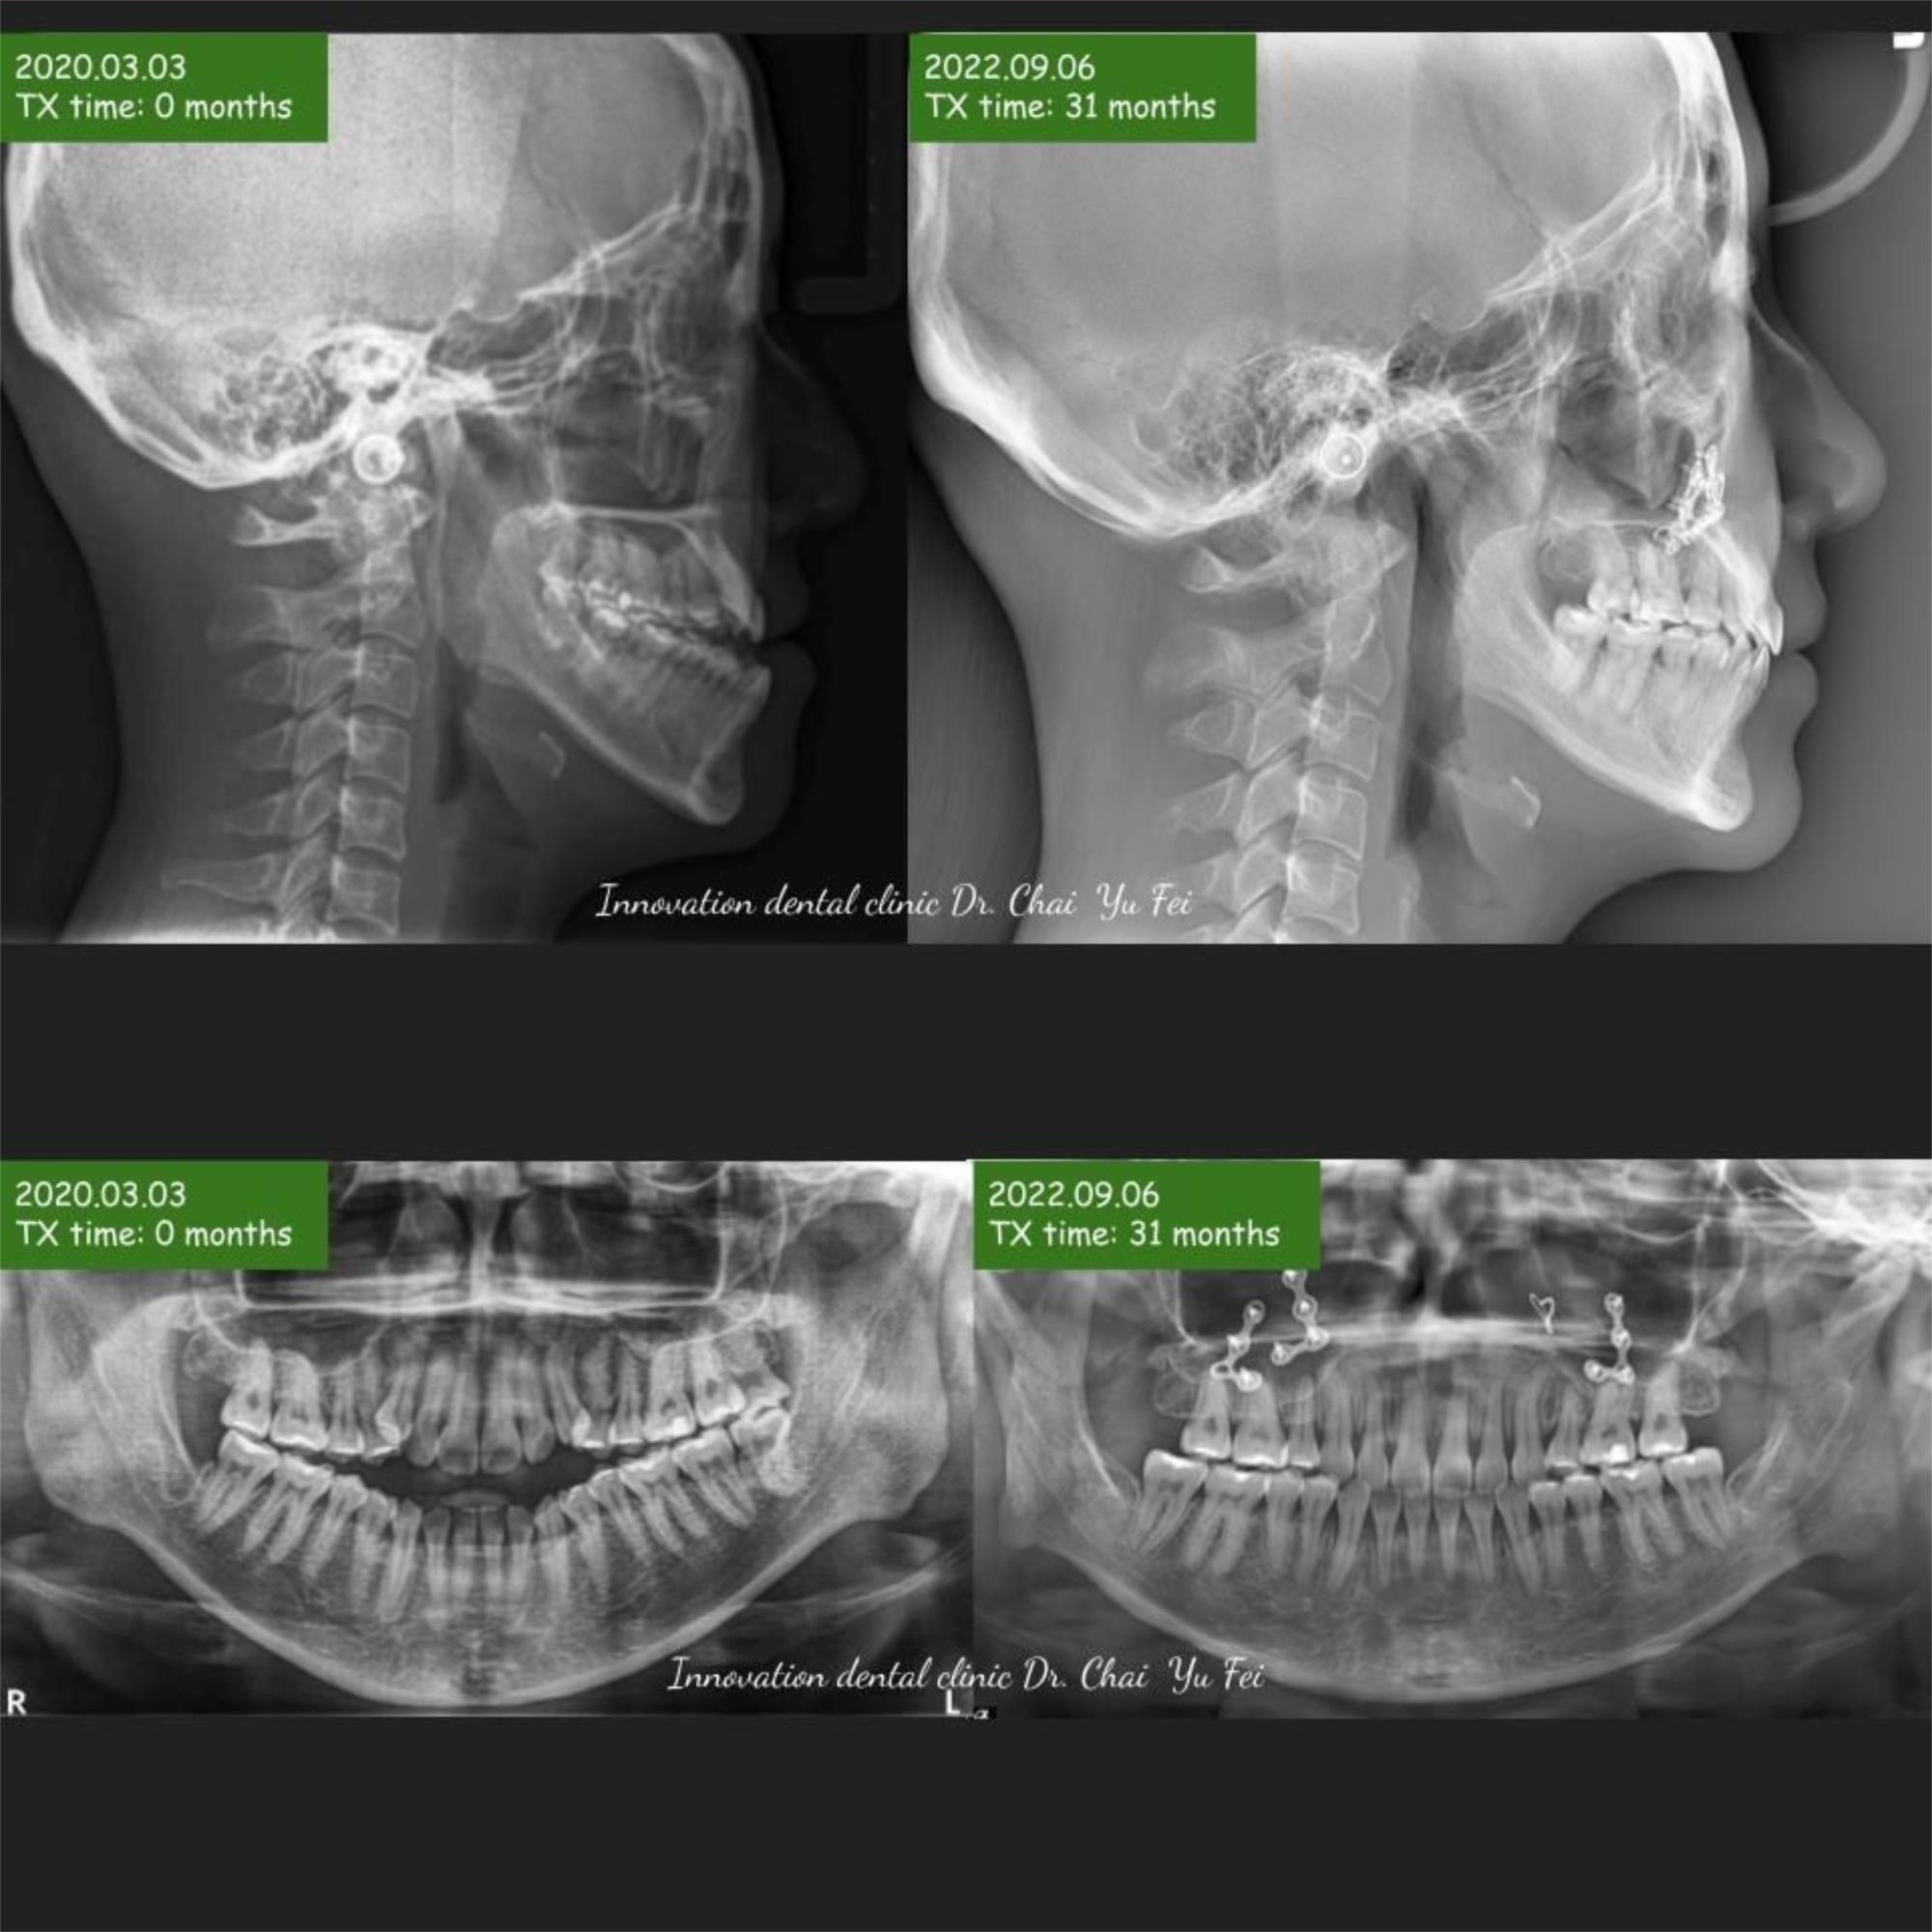

以這次分享的W同學案例來說,W同學原本就有很好的外型,只是因為骨性戽斗,造成咬合不正,前牙呈現開咬,這樣的狀態已經困擾她超過十年以上。因緣際會透過寰宇牙醫診所-林裕崧醫師介紹來展心展研做諮詢,經過我的臨床診斷後,斷定這是需要合併「正顎手術」的矯正案例,也因此我決定與「矯正跟口腔外科雙專科」的蔡佩晏學姊合作。

從術前的準備跟評估開始,蔡佩晏學姊就展現細心無比的一面,不斷提醒我合併手術需要留意的細節,手術當天也因為有術前兩造醫師的仔細評估、溝通、擬定治療計畫,從麻醉、移動骨頭位置、上鈦板固定到縫合傷口,高度技術密集的作業過程進行得非常順利,這當中也要特別感謝小綠學姊,在TABLE上的神手,幫助咬合對在一個很順的位置。

謝謝W同學忍受術後那些不方便的時刻,最終能有這樣的結果大家都很開心,很想跟大家說:OGS(正顎手術合併的矯正治療)其實不可怕,只要經過仔細評估與規劃,就可以很完美的調整臉型與咬合!

シャクレ、長い顔、アシンメトリなどはいずれもOGS(顎矯正手術:Le Fort1+BSSO;上下顎骨切り)によって治療が予定です。